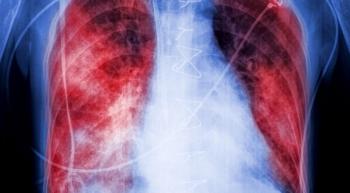

Lung cancer is the leading cause of cancer-related death for women in the United States, but often does not get as much attention as other malignancies. In an effort to change that, and to one day decrease the number of women who are dying from the disease, the bipartisan Women and Lung Cancer Research and Preventative Services Act was reintroduced into Congress.

Not all patients with non-small cell lung cancer (NSCLC) respond to immunotherapy, so researchers are exploring the use of combination regimens, including immune checkpoint inhibitors and chemotherapy, to improve outcomes in these patients.

Racial and socioeconomic status disparities can affect all types of lung cancer treatment – including surgery, chemotherapy and radiation. However, researchers may not be aware of this, since many of these groups are underrepresented in lung cancer clinical trials.